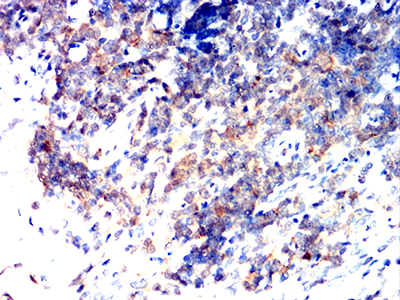

Immunohistochemical analysis of paraffin-embedded human cervical cancer tissues using BAX mouse mAb with DAB staining.